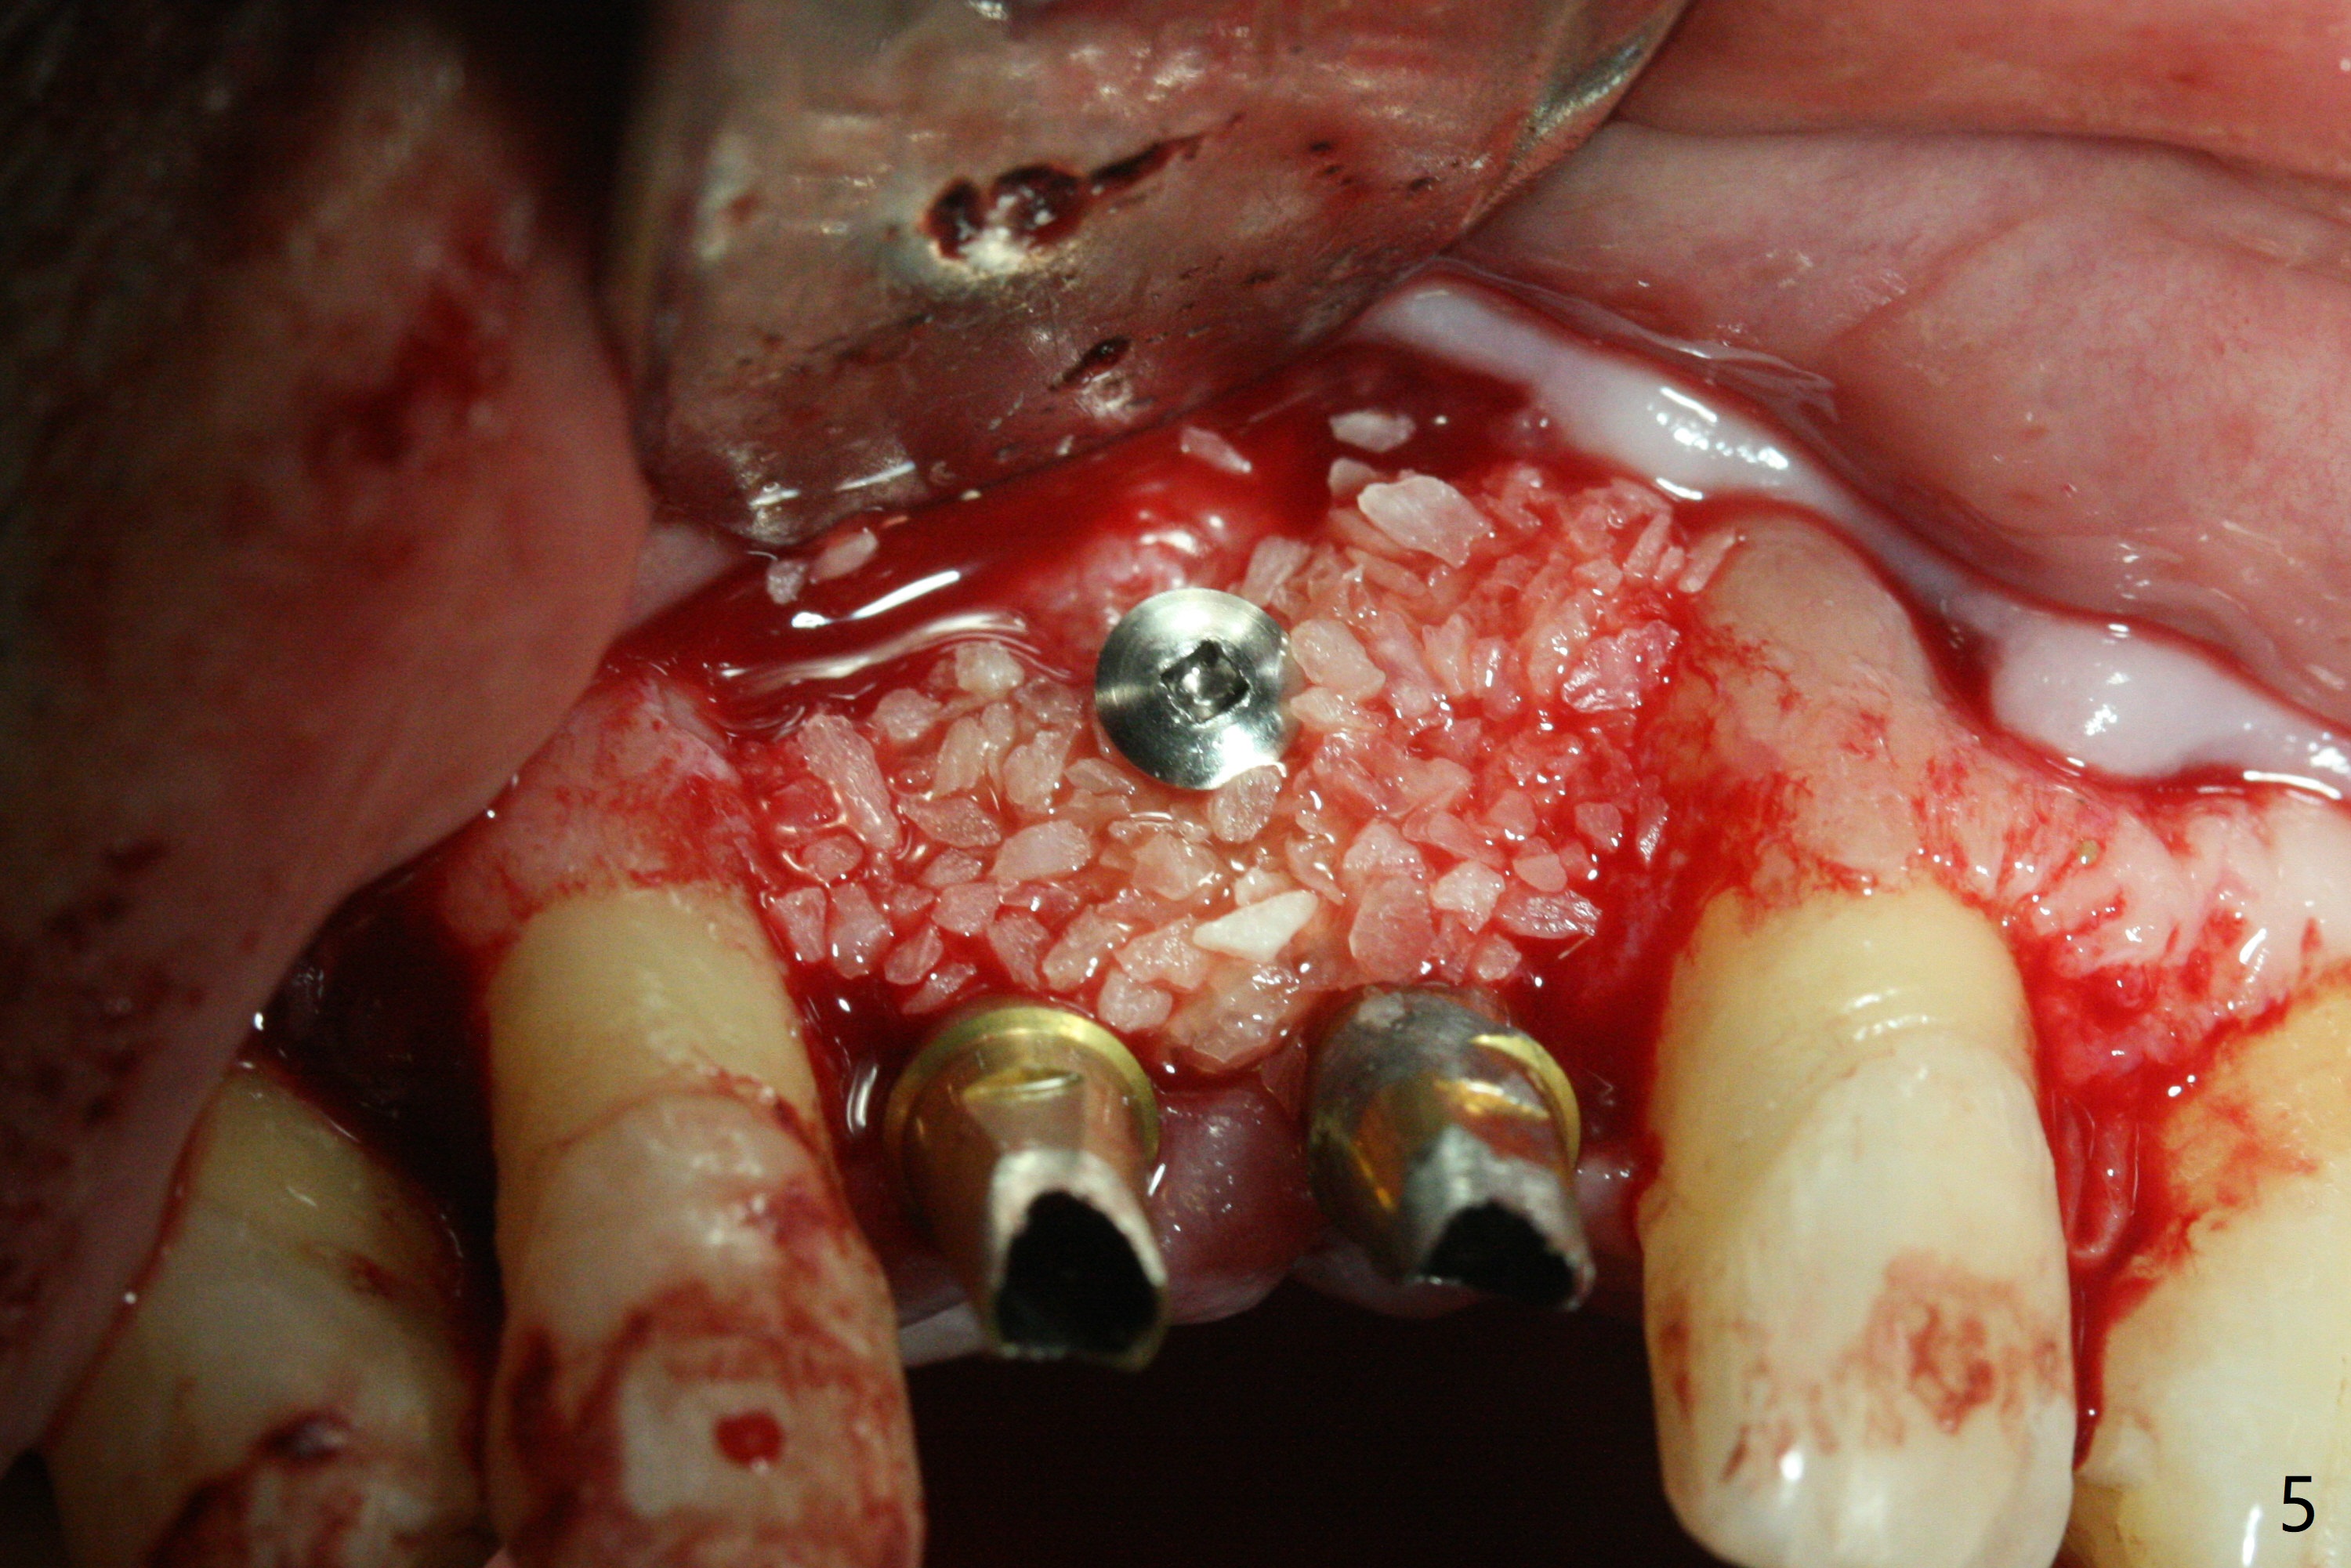

The gingiva remains recessive at #8 and 9 six months post immediate implant placement with bone graft (Fig.1). The buccal plate at #8 is particularly concave before (Fig.2 *) and after (Fig.3) abutment removal. The bony defect repair is assisted by placing a 4 mm tenting screw between the 2 implants (Fig.4) and placing allograft mixed with PRF (as putty) around the screw (Fig.5 (after replacement of the abutments)). The buccal contour improves because of the tenting screw and the bone graft placement (Fig.6 (as well as PRF and 6-month membranes)). The wound dehisces 12 days postop and immediately before leaving country for months (Fig.7). The sutures are removed, Osteogen plug is inserted (Fig.8) and periodontal dressing is applied (Fig.9). PA is taken to show the tenting screw (Fig.10 T). The latter is exposed 3 months postop (Fig.11,12). It appears that gingival graft is a must (Fig.13). Make a palatal stent, remove the temp with abutments and create a bleeding surface before harvesting a large piece of tissue. Connective tissue graft is done 5 months post bone graft (Fig.14). In fact there is no implant thread exposure. In fact the connective tissue graft does not survive. The abutments are re-prepared for pink porcelain (Fig.15). The bone loss is stable 1 year post cementation in spite of incomplete abutment seating (Fig.16). The soft tissue is nearly normal (Fig.17).